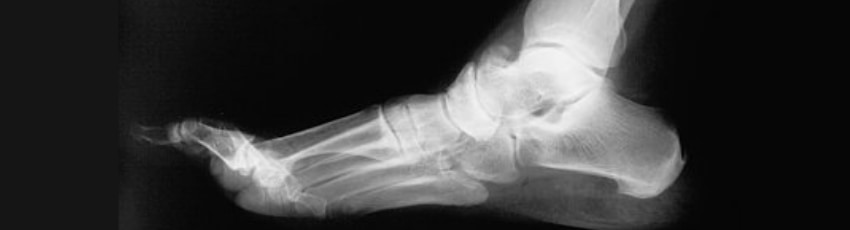

Orthopädische Diagnostik umfasst Anamnese, körperliche Untersuchung, Bildgebung (Röntgen, MRT, CT) und gegebenenfalls Labortests, um muskuloskelettale Erkrankungen zu identifizieren und die richtige Behandlung zu bestimmen.

Durch moderne Filter und Optimierung der Bildqualität lässt sich die Strahlenbelastung der Patienten so gering wie möglich halten. Bilder und Befunde können bei Bedarf leicht und platzsparend als Papierausdrucke oder auf CD gebrannt an unseren Patienten mitgegeben werden. Nebenbei entfällt die Umweltbelastung durch Entwicklungschemikalien.